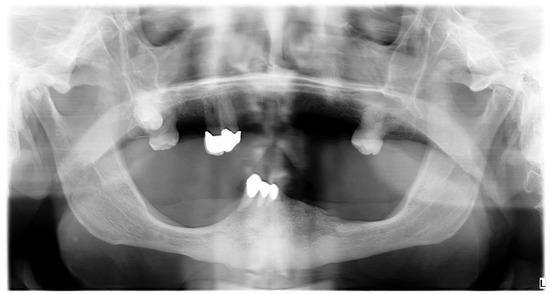

In March 2023, an 80-year-old ex-farmer male patient came to the Odontostomatology Unit of the “Aldo Moro” University of Bari (Italy) due to feeding difficulty. The cause of the patient’s main complaint was pain in the lower right incisors and the canine during chewing; these teeth showed grade III mobility. The patient showed an incompetent labial seal because of the anterior inclination of these teeth. The patient had microstomia and several ulcers on the lower lip. In addition, the patient showed a painful 3 cm area of ENB in the left region of the mandible (Figure 1 and Figure 2).

Figure 2. Panoramic Radiogram. The panoramic radiogram shows the osteolytic area overlapping with the lower left mandibular canal.